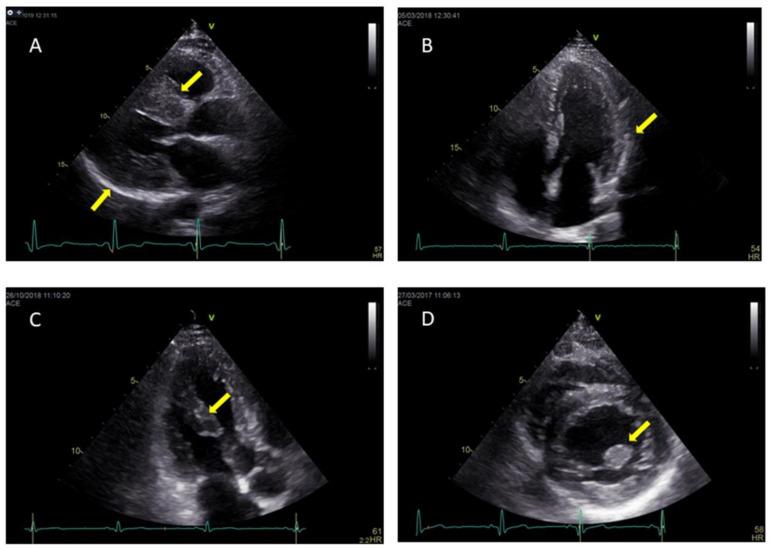

Anderson-Fabrydisease is an X-linked lysosomal storage disorder caused by a deficiency in the lysosomal enzyme α-galactosidase A. This results in pathological accumulation of glycosphingolipids in several tissues and multi-organ progressive dysfunction. The typical clinical phenotype of Anderson-Fabry cardiomyopathy is progressive hypertrophic cardiomyopathy associated with rhythm and conduction disturbances. Cardiac imaging plays a key role in the evaluation and management of Anderson-Fabry disease patients. The present review highlights the value and perspectives of standard and advanced cardiovascular imaging in Anderson-Fabry disease.

安德森-法布里病是一种X连锁溶酶体贮积症,由溶酶体酶α-半乳糖苷酶A缺乏引起。这导致糖鞘脂在多个组织中病理性蓄积以及多器官进行性功能障碍。安德森-法布里心肌病的典型临床表型是与节律和传导障碍相关的进行性肥厚型心肌病。心脏成像在安德森-法布里病患者的评估和管理中起着关键作用。本综述强调了标准和先进心血管成像在安德森-法布里病中的价值和前景。